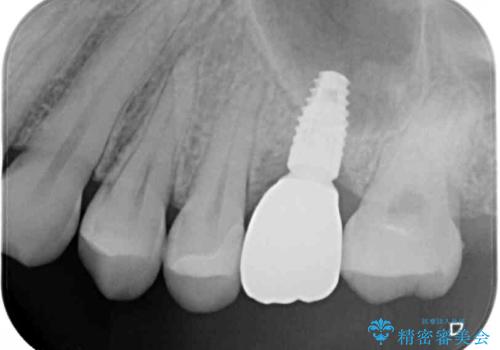

土台の材料を外して顕微鏡下で確認したところ、歯根にまで及ぶ破折が認められたため、インプラント治療を行うこととしました。

インプラント治療をきっかけに、銀歯を全てセラミックに替えていきました。